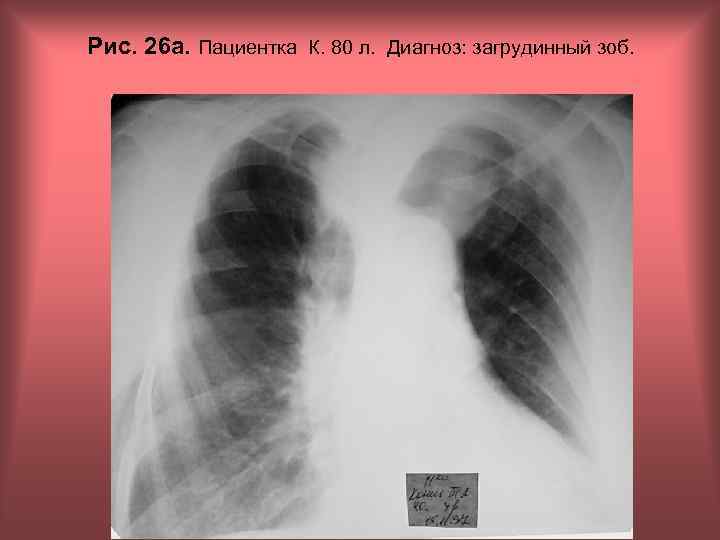

Рис. 26 а. Пациентка К. 80 л. Диагноз: загрудинный зоб. Н. С. Воротынцева, С. С. Гольев Рентгенопульмонология